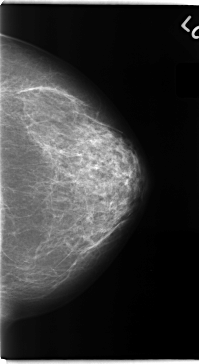

C_0151_1.LEFT_CC

LEFT_CC LINES 4728 PIXELS_PER_LINE 2584 BITS_PER_PIXEL 12 RESOLUTION 50 NON_OVERLAY